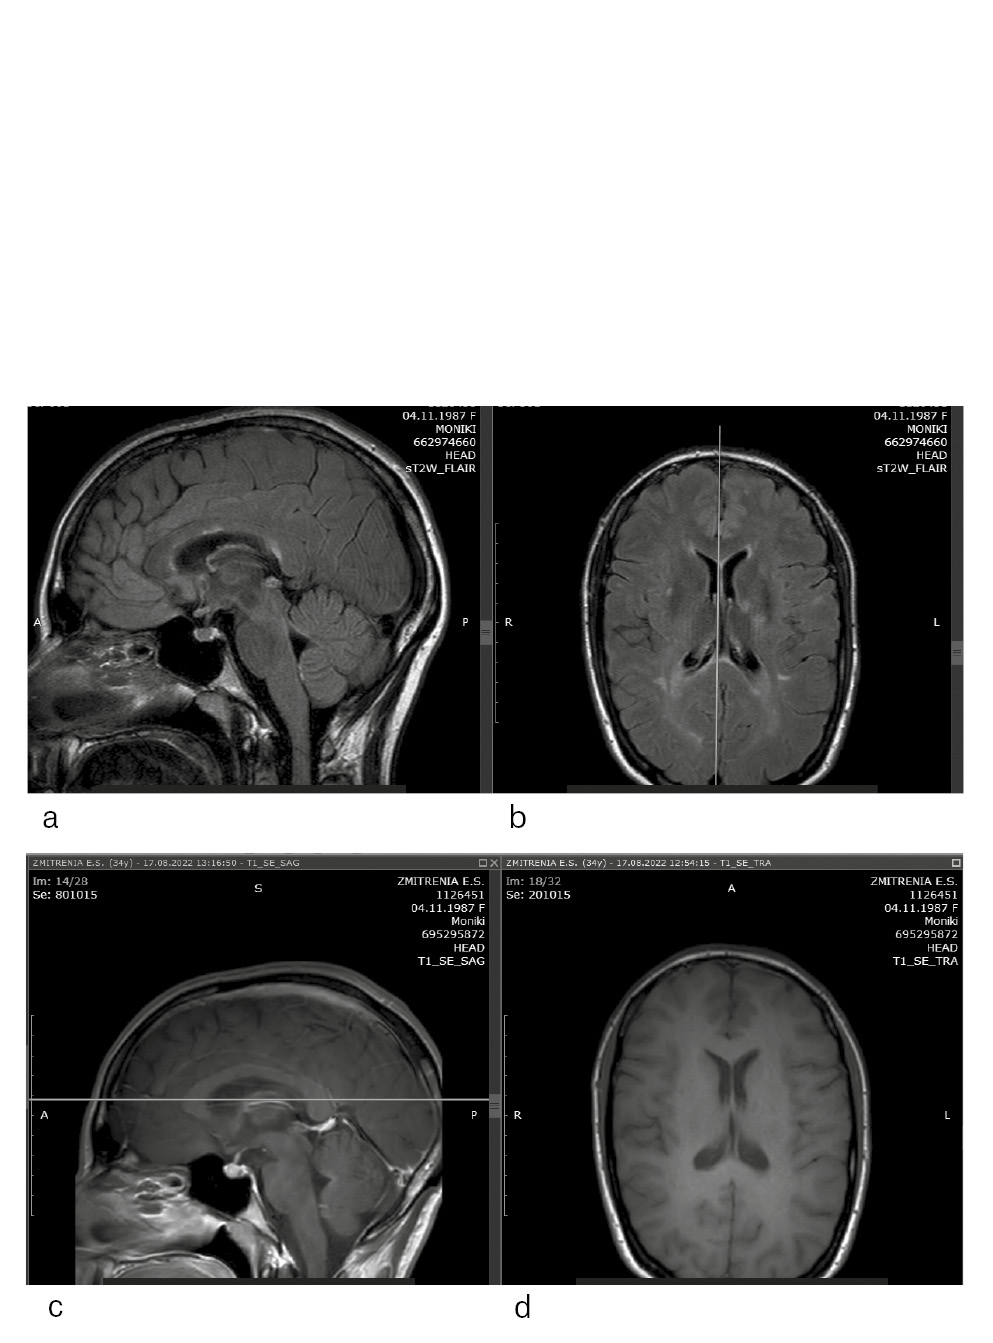

Анализ СМЖ: прозрачная, бесцветная, белок – 0,41 г/л, реакция Панди положительная, глюкоза – 2,9 г/л, цитоз – 1 клетка в мкл, 100% лимфоцитов; ДНК цитомегаловируса, ДНК вируса Эпштейна–Барр, ДНК вируса простого герпеса I и II типа, ДНК Candida albicans, ДНК Varicella Zoster virus, ДНК Toxoplasma gondii, Mycobacterium tuberculosis не обнаружены. Выявлен 2-й тип синтеза олигоклонального характера иммуноглобулина G в ликворе и поликлонального синтеза иммуноглобулина G в сыворотке крови. Проведено МРТ головного мозга на высокопольном аппарате с индукцией магнитного поля 3 Тесла (рис. 1).

Рис. 1. МРТ головного мозга пациентки К. Изображения получены в аксиальной и сагиттальной плоскостях до и после контрастного усиления: а–c – в режимах T2ВИ, FLAIR; d, e – в режиме T1ВИ. Визуализируются патологические зоны сигнала в стволовых структурах: мосту, правой половине продолговатого мозга, с переходом по правой средней ножке мозжечка в верхнюю половину правого полушария мозжечка, без четких контуров и границ, неправильной формы, одиночные разнокалиберные очаги в субкортикальных отделах белого вещества больших полушарий, гиперинтенсивные в режимах Т2ВИ и FLAIR. Накопления контрастного вещества не отмечается.